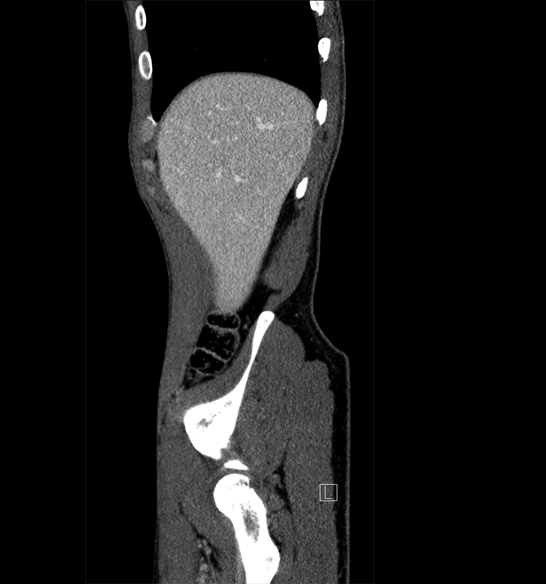

Body

Covers abdominal CT anatomy.